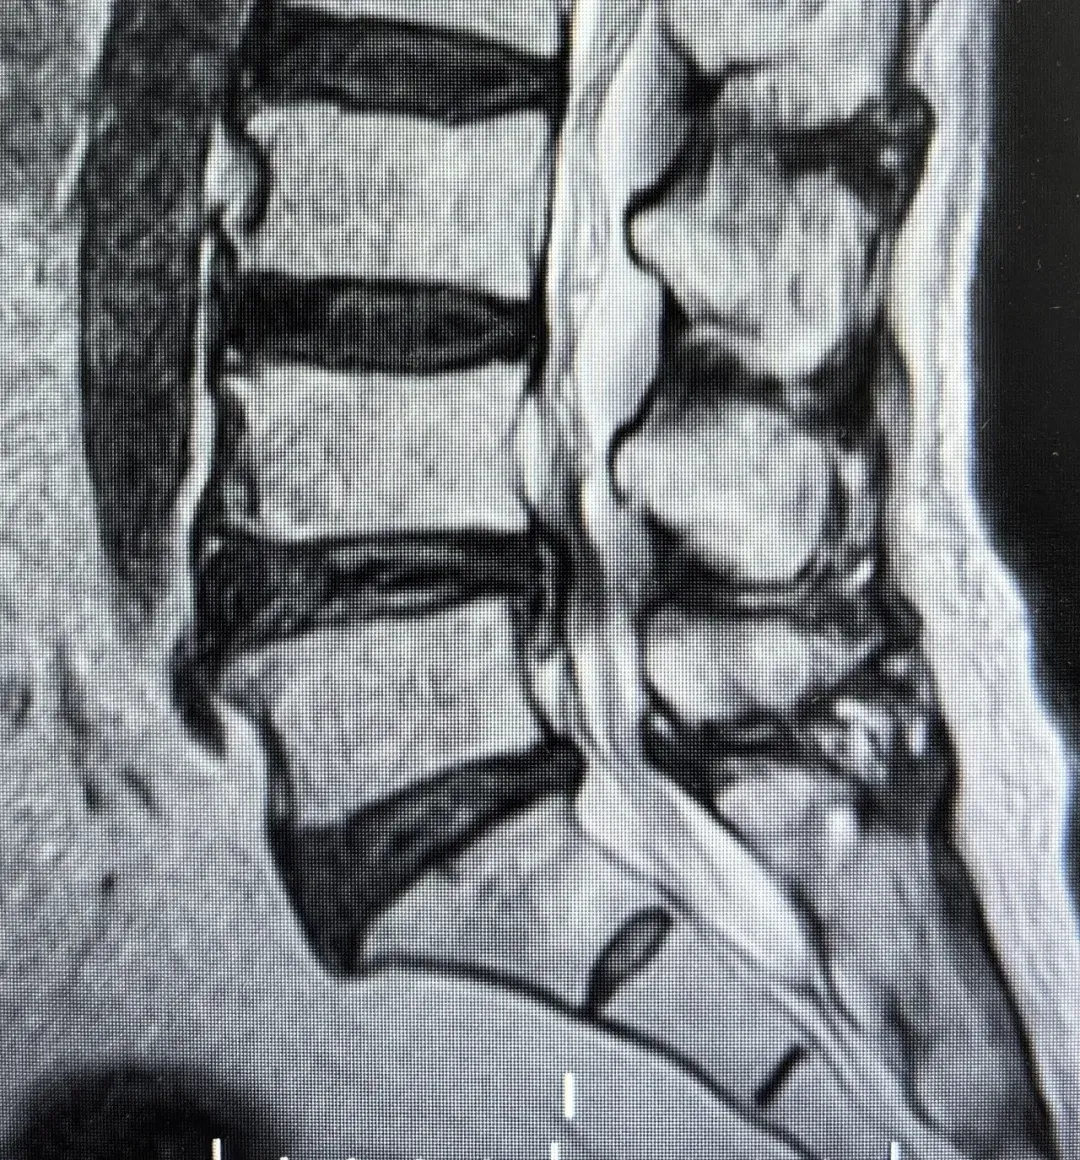

IMG_256 李龍主任詳細閱讀影像學資料并再次對患者進行全面評估,明確了病因:腰4-5節(jié)段重度椎管狹窄合并腰椎失穩(wěn)。這正是導致患者下肢劇烈疼痛和行走困難的“罪魁禍首”。李主任向患者及家屬詳細解釋了病情:椎管狹窄使得神經受壓,腰椎失穩(wěn)則加劇了這種壓迫和炎癥反應,保守治療在此階段難以解決根本問題。他建議施行微創(chuàng)減壓融合術,徹底解除神經壓迫,重建腰椎穩(wěn)定。 IMG_258 當聽到可以通過手術進行“減壓”時,被病痛折磨多年的老人仿佛看到了曙光,如同抓住了“救命稻草”。在充分理解手術必要性與微創(chuàng)技術的優(yōu)勢后,患者及家人消除了對高齡手術的恐懼,果斷接受了李龍主任提出的手術方案。經過周密的術前準備,手術如期進行。李龍主任團隊憑借精湛的微創(chuàng)技術,成功為患者實施了腰4-5微創(chuàng)減壓融合術。手術過程順利,術中出血極少。術后,困擾患者多年的腿疼癥狀得到了很大緩解。令人欣喜的是,在術后第三天,老人便在醫(yī)護人員指導下,佩戴支具下地行走。邁步的那一刻,患者及其家屬的臉上露出了久違的笑容。對梁振斌主任的精準初判、李龍主任的高超技術以及整個醫(yī)療團隊的精心照護表示了無盡的感激。 IMG_260 本例高齡患者的成功救治,充分體現(xiàn)了精準診斷、多學科協(xié)作以及現(xiàn)代脊柱微創(chuàng)技術的巨大優(yōu)勢。李龍主任提醒,如果腰腿痛長期保守治療無效,特別是疼痛加重、行走越來越困難的患者,應盡早到正規(guī)醫(yī)院就診,由醫(yī)生評估是否需要手術。微創(chuàng)手術技術成熟,可以為許多高齡、高風險患者提供安全有效的治療,避免延誤病情導致神經不可逆的損傷。(李 ? 勇)